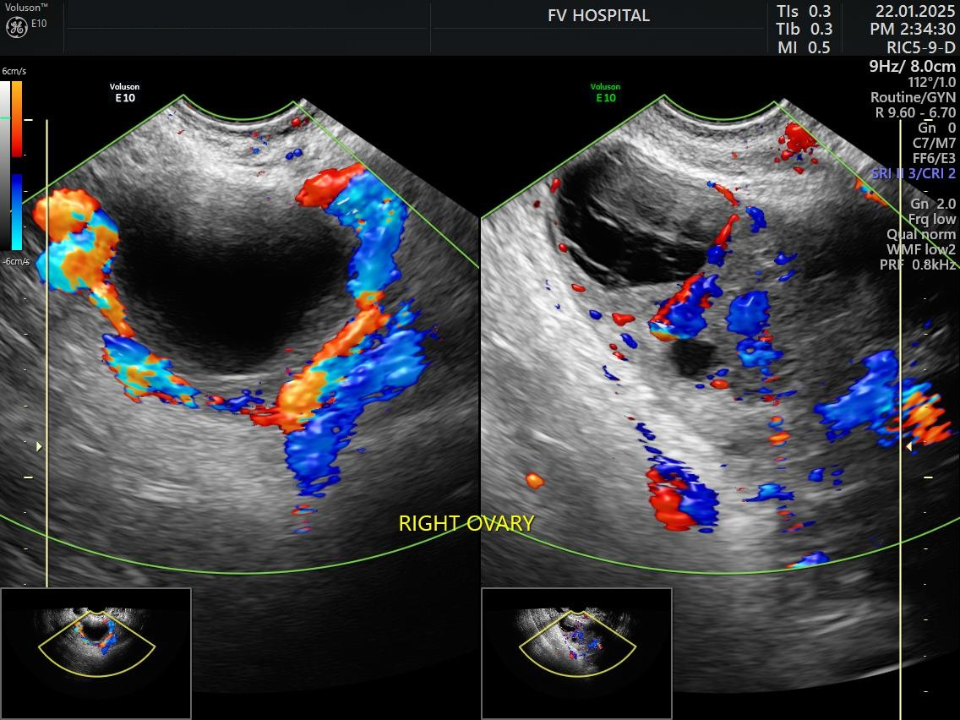

Chị X.A., 30 tuổi, đến Bệnh viện FV với triệu chứng đau nhẹ vùng hố chậu phải. Sau 24 giờ, cơn đau tăng đột ngột, kèm buồn nôn, nôn ói. Siêu âm cho thấy buồng trứng phải phình to gần gấp đôi. ThS.BS Võ Triệu Đạt lập tức yêu cầu hội chẩn liên chuyên khoa với các chuyên gia ngoại khoa và chẩn đoán hình ảnh. Kết luận sau hội chẩn cho thấy đây là tình trạng xoắn phần phụ buồng trứng ở bệnh nhân mang thai 5–6 tuần.

Chị X.A được phẫu thuật nội soi cấp cứu ngay lập tức. Ngay sau khi tháo xoắn, buồng trứng dần hồi phục tưới máu - dấu hiệu cho thấy đã được can thiệp kịp thời. Bệnh nhân xuất viện sau 2 ngày, thai kỳ phát triển ổn định.

Hình siêu âm tái khám sau 1 tuần: bên trái buồng trứng xoắn, bên phải buồng trứng đã được tưới máu lại bình thường sau phẫu thuật. (Ảnh: FV)